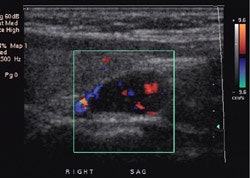

On ultrasound, adenomas typically appear as homogenenous oval anechoic or hypoechoic discrete masses posterior to the thyroid gland, anterior to the longus coli muscle, and medial to the carotid artery. Color doppler will show a characteristic extrathyroidal feeding vessel (generally a branch off the inferior thyroid artery) entering the gland at one of the poles [24]. Vascularity tends to be is a peripheral distribution [24]. Pre-operative ultrasound has a sensitivity of 34-85%, and a specificity of 77-98% for the detection of parathyroid adenomas [2,3,15,18,21]. However, in a large meta-analysis, sonographic sensitivity for the detection of a solitary adenoma was 79% (95% CI 77-80%), for hyperplasia it was 35% (CI 30-40%), and for double adenomas it was 16% (CI 4-28%) [24]. The sensitivity falls to about 40% in patients who have prior failed surgical explorations [21]. Identification of a prominent feeding vessel with color Doppler can aid in the detection of abnormal glands [3]. A small lymph node can mimic a parathyroid adenoma. Sonography is less sensitive in the detection of parathyroid hyperplasia [3]. The reliability of sonography is very low for ectopic glands located in the mediastinum. In general, a preoperative approach that combines the both anatomic information of US and the physiologic information of scintigraphy has been shown to predict the presence and location of solitary adenomas more accurately than either technique alone [24].

Parathyroid adenoma on ultrasound: A Tc-MIBI exam demonstrated findings consistent with a parathyroid adenoma in the lower right neck. US exam confirmed the presence of a well-circumscribed, vascular hypoechoic nodule below the lower pole of the right lobe of the thryoid. This was a parathyroid adenoma at surgery. |